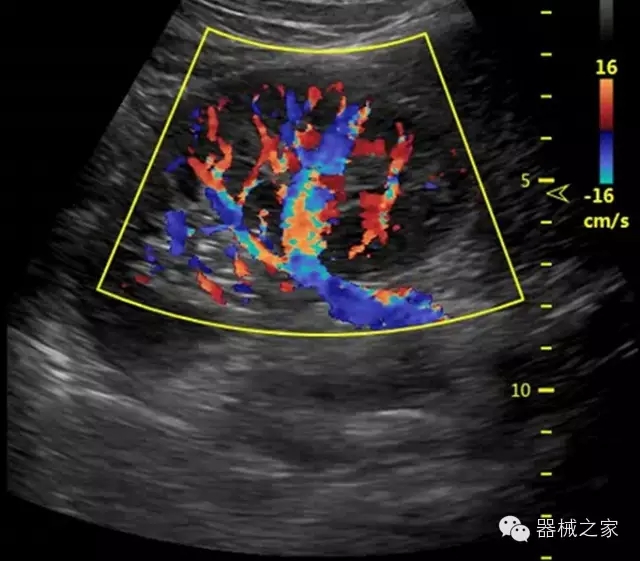

臨床圖片賞析

·獨(dú)有的RF平臺提高微小細(xì)節(jié)顯示、圖像對比度和邊界清晰度;

·特有的XCEN探頭,超寬的帶寬,表現(xiàn)更高分辨率和對比度;

·單晶純凈波探頭提供更佳的穿透力和彩色敏感度;

·完整的3D/4D臨床應(yīng)用,STIC, MCUT 和Auto NT等滿足產(chǎn)科所有應(yīng)用;

·更高的HQ羊膜腔鏡成像技術(shù)精細(xì)觀察每一個(gè)暗區(qū)細(xì)節(jié);

·智能的觸摸屏界面,能任意角度方位旋轉(zhuǎn)3D圖像,以及注釋快速標(biāo)記,提供直觀與便捷的操作,提高了工作效率;

·飛依諾特有心臟純凈波探頭提供更好的穿透力和彩色敏感度,以及結(jié)合TView梯形拓展改善困難病人深部組織成像;

·獨(dú)有RF敏感血流使得心臟血流完美呈現(xiàn);